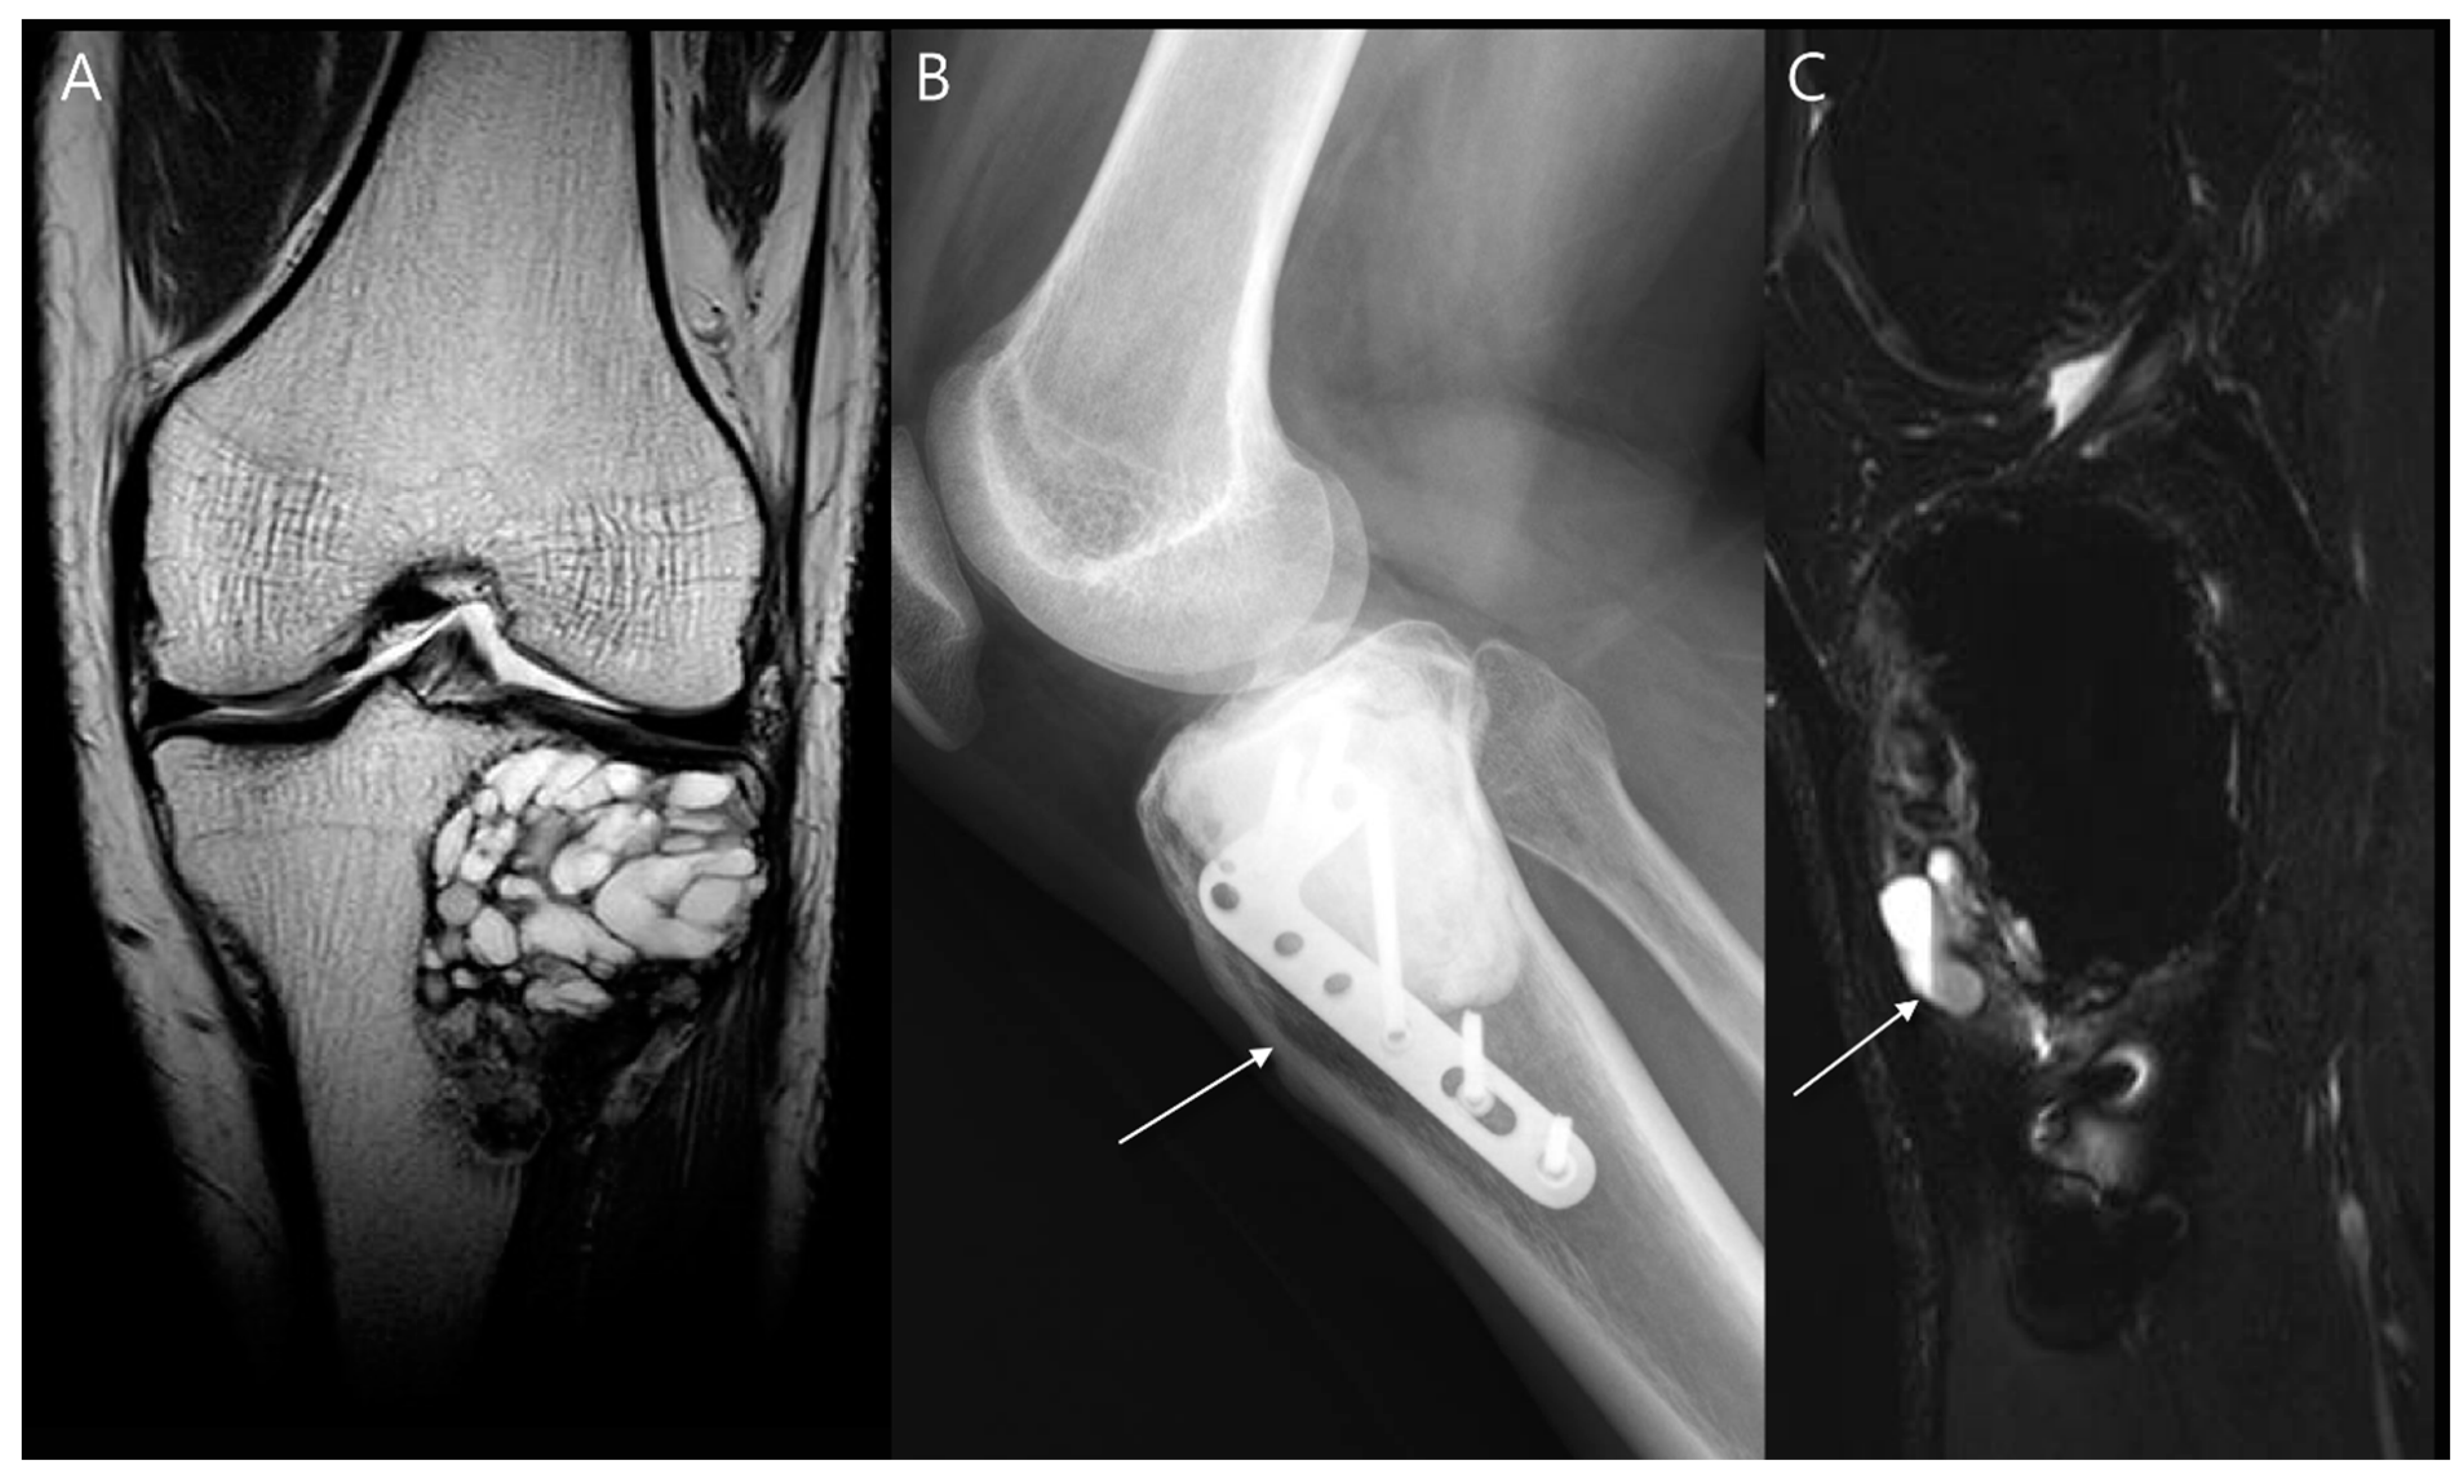

- Turcotte, R.E.; Stavropoulos, N.A.; Toreson, J.; Alsultan, M. Radiographic assessment of distal femur cemented stems in tumor endoprostheses. Eur. J. Orthop. Surg. Traumatol. 2017, 27, 821–827. [Google Scholar] [CrossRef]

- Henderson, E.R.; Groundland, J.S.; Pala, E.; Dennis, J.A.; Wooten, R.; Cheong, D.; Windhager, R.; Kotz, R.I.; Mercuri, M.; Funovics, P.T.; et al. Failure mode classification for tumor endoprostheses: Retrospective review of five institutions and a literature review. J. Bone Jt. Surg. 2011, 93, 418–429. [Google Scholar] [CrossRef]

- Shah, A.; Cardoso, F.N.; Souza, F.; Montreuil, J.; Pretell-Mazzini, J.; Temple, H.T.; Hornicek, F.; Crawford, B.; Subhawong, T.K. Failure Modes in Orthopedic Oncologic Reconstructive Surgery: A Review of Imaging Findings and Failure Rates. Curr. Oncol. 2024, 31, 6245–6266. [Google Scholar] [CrossRef]

- Song, E.H.; Lee, S.Y.; Lee, S.; Jung, J.Y.; Shin, S.H.; Chung, Y.G.; Jung, C.K. Diagnosis of Local Recurrence of Malignant Soft Tissue Tumors after Reconstructive Surgery on MRI. J. Clin. Med. 2023, 12, 4369. [Google Scholar] [CrossRef]